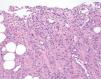

En el estudio histológico de la arteria se observó una pared engrosada con un moderado infiltrado inflamatorio crónico compuesto por linfocitos, histiocitos, algún eosinófilo, y focalmente alguna imagen sugestiva de células gigantes, localizado en las capas media y adventicia (fig. 1).